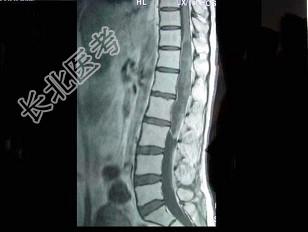

- 单项选择题男,43岁, 背部疼痛,双下肢瘫痪, 查体:下腹部以下深浅感觉障碍, 提睾反射消失,结合图像, 最可能的诊断是 ( )

A、星形细胞瘤

B、脑膜瘤

C、神经鞘膜瘤

D、神经纤维瘤

E、髓内室管膜瘤